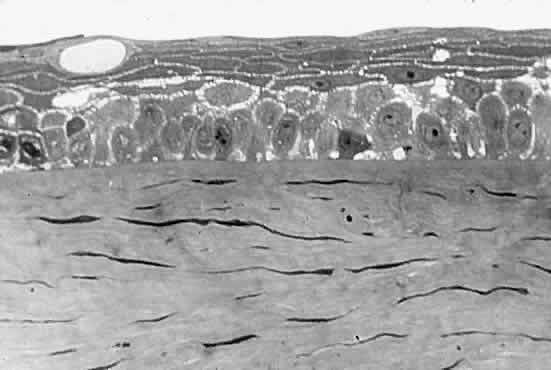

But how can the cornea be so clear if it is made of structures as diverse as epithelial cells, collagen fibers (refractive index, 1.47), and a ground substance whose refractive index is close to that of water (1.333)? The epithelial cell layer may be considered as homogeneous units of a protein solution, with each cell so tightly packed against the next that almost no extracellular water accumulates and there is virtually no fluctuation in refractive index throughout the layers. In the stroma, the collagen fibers are approximately 25 nm in diameter, and the spacing between each pair of fibrils is 60 nm. These dimensions are much smaller than a wavelength of yellow light (600 nm).4 Thus, the tiny dimensions and regular arrangement of these fibrils (Fig. 5) account for the minimal scattering.

Fig. 5. Top. Electron micrograph shows the arrangement of collagen fibers in normal corneal stroma. Bottom. Electron micrograph of a corneal stroma with edema. Note the irregular collection of fluid. (Miller D, Benedek G: Intraocular Light Scattering. Springfield, IL, Charles C Thomas, 1973. Courtesy of T. Kuwabara, Howe Laboratory, Harvard Medical School)

CORNEAL STROMAL EDEMA

In cases of endothelial dystrophy, endothelial trauma, or endothelial incapacitation due to inflammation (i.e., iritis), the pumping action of the endothelium diminishes and the stroma takes on additional fluid and thickens. As interfibrillar fluid increases, the collagen fibers are pushed farther and farther apart. As the lakes of such fluid exceed one half of a wavelength of light in dimension, light scattering increases and the cornea takes on a gray appearance (see Fig. 5).4